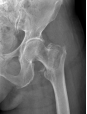

为提升区域内基层医疗机构糖尿病足诊疗服务能力、促进青年医师对糖尿病足的规范化诊治水平,遵义市第二城市医疗集团总院(贵州航天医院)圆满举办贵州省继续医学教育项目——胫骨横向骨搬移技术治疗糖尿病足专题研讨班。 贵州航天医院党委委员、副院长彭亮出席会议并致辞,遵义市第二城市医疗集团各成员单位,以及红花岗区、汇川区、绥阳县、桐梓县等多个区县的基层医疗机构骨干医师参加会议。 研讨班 本次研讨班以胫骨横向骨搬移技术在糖尿病足治疗中的应用为核心主题,围绕糖尿病药物治疗与生活方式管理策略、围手术期血糖精准调控要点、胫骨横向骨搬移技术典型病例深度解析、糖尿病足的临床分型与个体化治疗方案制定等临床实践中的热点与难点展开深入探讨,通过专题授课、案例研讨、互动交流等多元化形式,为参会者搭建了理论与实践结合的学习平台。 此次研讨班不仅为区域内基层医院搭建了学术交流与经验共享的平台,更对推动糖尿病足预防、诊断与治疗的规范化、系统化发展起到了积极作用,有效助力青年医师更新专业知识体系、提升临床技能,为进一步保障区域内糖尿病足患者的健康奠定了坚实基础。 贵州航天医院骨科专家简介 陈明勇 骨一科主任,副主任医师 临床擅长:从事创伤骨科工作约20年,对骨缺损、骨不连、骨肿瘤、肢体畸形等的肢体矫形重建及功能重建,慢性化脓性骨髓炎的根治治疗、糖尿病足的保肢治疗、快速康复理念(ERAS)下的老年骨折的诊治,四肢复杂骨折的诊治,四肢骨折等微创手术治疗具有丰富的临床经验。 2004年毕业于遵义医学院临床专业,曾在中国人民解放军总医院、广西医科大学第一附属医院、上海第六人民医院骨科进修。中国中西医结合学会骨伤科专业委员会横向骨搬移治疗糖尿病足及微血管网再生学组首届委员,遵义市医学会创伤分会常务委员。 瞿 晖 骨科党支部书记,骨二科主任,副主任医师 临床擅长:对骨科的常见病、关节外科、脊柱外科及运动医学疾病的诊治具有丰富的临床经验,熟练掌握骨科手术操作技术。 毕业于遵义医学院临床医学系,2005年前往广州中山大学第一附院骨显微医学部进修学习,2011年前往成都华西医院进修学习,并多次在省内外学习骨科相关知识,是中华医学会骨科分会会员。 赵小锋 中共党员,骨二科副主任,副主任医师 临床擅长:从事骨科临床工作11年,对骨科常见病、多发病诊疗有较为丰富的临床经验,擅长脊柱相关疾病诊断及治疗,尤其是颈、腰、腿疼痛疾病诊断及治疗,擅长胸腰椎骨折微创经皮穿刺内固定术、经皮穿刺椎体成形术、经皮穿刺脊柱内镜下腰椎间盘摘除术、单纯开创腰椎间盘摘除术、腰椎滑脱复位椎间植骨椎融合内固定术、腰椎管狭窄减压融合内固定术及人工髋、膝关节置换术等。 2012年毕业于遵义医学院外科学专业硕士研究生,2019年参加“遵义市115医学人才精英计划”于上海交通大学第一附属医院培训学习,2023年于北京大学第三人民医院脊柱外科进修学习,曾获得遵义市优秀医师荣誉称号。 遵义市手外科第一届委员,遵义市医学会创伤分会第一届委员,遵义市医学会创伤分会第二届委员,贵州省康复医学会第三届脊柱脊髓专业会委员,遵义市医学会烧伤与整形外科学分会委员,发表论文5篇,其中国家级核心期刊1篇,SCI论文1篇,主持市级课题1项并结题,参与市级课题2项。 赵兴东 骨科主任医师 临床擅长:擅长骨科的常见病及各种创伤、四肢骨折创伤修复、骨感染、手足疾病的诊治和手足体表畸形的矫形整复,熟练掌握骨科四肢骨病及创伤的手术操作技术,尤其在四肢关节复杂性损伤、手足外伤、组织缺损创面、难治创面的皮瓣修复方面及平足、高弓足矫形方面及四肢慢性疼痛诊治、康复方面具有丰富的临床经验。 硕士研究生,毕业于遵义医学院临床外科系,2015年前往山东省立医院手足外科进修学习;遵义市医学分会创伤分会第一、二届委员,遵义市手外科医学会第二委届员会常务委员;在省级及省级以上期刊发表文章9篇,参编著作2部,参与主持并完成市级课题1项,参与市级课题2项、省级课题1项。 张艳金 中共党员,骨科副主任医师 临床擅长:从事骨外科工作16年,对复合伤、多发伤的救治、四肢骨干骨折、关节周围骨折、骨肿瘤、骨髓炎等诊治具有丰富的临床经验。 中共党员,硕士研究生,2006年本科毕业于山西医科大学第二临床医学院,2011年研究生毕业于北京军区总医院;在“老年COPD患者合并髋部骨折的诊治”国际合作课题组研究两年,在老年髋部骨折的诊治方面具有丰富的经验,并发表论文6篇;主持遵义市级课题1项,承担遵义医科大学的临床教学工作,获得遵义医科大学优秀带教老师荣誉。编撰有《骨科疾病诊疗精粹》一书,开展2项新技术,编撰地方规范《务川自治县创伤骨科常见疾病诊疗规范》一书。 张俊凯 骨科副主任医师 临床擅长:从事骨科临床工作28年,对创伤骨折、骨感染、骨缺损、骨不连等外科诊治,四肢骨折的微创手术治疗,四肢复杂骨折(如关节内粉碎性骨折、多发骨折等)的损伤控制及手术治疗等具有丰富的临床经验。 1995年毕业于遵义医学院临床专业,2009年前往复旦大学附属医院骨科进修1年。 卢懿明 中共党员,骨科副主任医师 临床擅长:从事骨科工作18年,对创伤骨折、四肢骨折的微创手术治疗、四肢复杂骨折(如关节内粉碎性骨折、多发骨折等)的损伤控制及手术治疗,尤其是髋部骨折的PFNA等微创技术,踝关节骨折、膝关节周围骨折的Mipo微创技术等具有丰富的临床经验,开展了4项新技术,发明6项新型专利技术。 2005年毕业于遵义医学院临床专业,2017年,前往南方医科大学第三附属医院骨科进修半年,回院后运用Mipo技术对骨干骨折及干骺端骨折的治疗技术,同时积极开展骨盆骨折、髋臼骨折腹直肌外侧切口的应用;发表了多篇专业论文,经常参与省内外学术交流会授课,获得医院荣誉称号多个。 邬夏荣 骨科副主任医师 临床擅长:从事骨科工作16年,对四肢复杂骨折、骨肿瘤的诊治,尤其是足踝创伤、慢性踝关节损伤、平足症等诊疗具有丰富的临床经验。 2006年毕业于遵义医科大学临床医学专业,曾在陆军军医大学西南医院进修学习,发表多篇骨科学术论文。 余德怀 中共党员,骨科副主任医师 临床擅长:从事骨科工作10余年,对运动医学、骨关节、脊柱外科常见病、多发病的诊治具有丰富的临床经验。 硕士研究生,2011年毕业于遵义医学院临床医学专业,曾前往遵义医科大学附属医院运动医学专业进修学习;是贵州省医学会运动医学分会青年委员,西部关节镜联盟委员;发表多篇骨科学术论文。 冯 乾 骨科副主任医师 临床擅长:从事骨科工作近20年,熟练掌握骨科多发病及常见病的诊治,尤其对脊柱退变性疾病的诊断及治疗具有丰富的临床经验,主要研究脊柱微创相关治疗方式,能熟练开展椎间孔镜及UBE。 曾前往北京大学第三医院进修学习疼痛及椎间孔镜、首都医科大学友谊医院专业进修脊柱内镜;是贵州省康复医学会第三届脊柱脊髓专业委员会委员;发明专利3项、发表脊柱外科专业论文多篇。 贵州航天医院骨科简介 基本情况 贵州航天医院(原3417医院)骨科组建于1968年,前身是以创伤和断肢(断指)再植闻名于世的上海市第六人民医院骨科,中国断肢(断指)再植的奠基者、中科院院士陈仲伟等专家莅临科室指导医疗和教学,并在70年代开展了贵州省首例断肢(断指)再植手术。组建50余年来,诊治患者已逾百万,挽救了无数的伤病员,成为了保障遵义地区人民群众健康的重要支撑。 经过几代人的不懈努力,今天的骨科,已由创伤骨科发展至骨病、骨肿瘤、骨结核等领域,现有脊柱外科、关节外科、四肢创伤、手足外科四个亚专科,成为了集医疗、教学、科研于一体的综合学科,是贵州省临床重点专科、遵义市临床重点专科、遵义市骨科临床医学中心、遵义市基层骨科专科联盟理事长单位。 科室目前开放床位110张,共有医护人员50余人,副高级以上专家18人,硕士研究生15人。拥有一流骨科医疗设备多台,每年不定期选派优秀技术骨干到全国各大知名医学院校进修、学习、参观、交流,并邀请国内、国外知名专家教授来院进行交流、指导,通过不断引进国内外先进的诊疗技术,科室医疗技术水平稳步提升,为广大人民群众提供了优质的医疗服务。 专科特色 骨一科 (一)骨缺损、骨不连的肢体与功能重建 胫骨横向骨搬移技术治疗糖尿病足: (二)慢性骨髓炎的根治治疗 (三)肢体缺血性疾病如糖尿病足、脉管炎的保肢治疗 (四)皮瓣修复 (五)复杂创伤的治疗 (六)老年髋部骨折及小儿骨折快速手术 老年髋部骨折: 骨二科 (一)胸腰椎骨折微创经皮椎弓根螺钉固定术 (二)老年性骨质疏松性患者腰椎滑脱脊柱内固定术(骨水泥螺钉) (三)V形双通道脊柱内镜技术(VBE)腰椎融合术治疗腰椎退行性疾病 (四)老年性骨质疏松性骨折(PVP/PKP)术 (五)人工髋关节置换术 (六)双侧股骨头坏死人工全髋关节置换 (七)右侧全髋置换术后假体周围骨折翻修 (八)人工膝关节置换术 (九)人工膝关节假体松动翻修 (十)关节镜技术 传统手术切口 关节镜技术切口 诊疗范围 骨一科 1.四肢创伤、矫形。 2.手、足踝外科。 骨二科 End